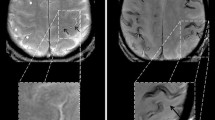

T2*-weighted gradient-echo MRI in a 58-year-old patient suffering from aneurysmal SAH. First MRI 22 days after SAH (a) shows blood residues in the central sulcus and parietal sulci on the right side (arrow). Nearly 1 year later (b), hemosiderin can still be observed in the central sulcus and in parietal sulci on the right side (b; arrows). Hemosiderin depositions appear as hypointense lines

CT on admission (a) and T2*-weighted gradient-echo MRI after 1 year (b) in a 78-year-old patient suffering from aneurysmal SAH. CT on admission shows blood in the central sulcus on the left side (arrow). One year later (b), hemosiderin can be seen in the central (arrow) and postcentral sulcus on the left side. Note that signal in the affected sulci is hyperintense whereas both surfaces of the adjacent cortices show thin linear hypointensities (tram-track sign). This is characteristic of cortical hemosiderosis